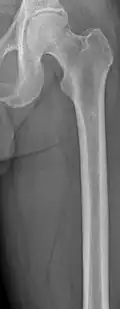

Medical imaging

The diagnostic examination of a person with suspected multiple myeloma typically includes a skeletal survey. This is a series of X-rays of the skull, axial skeleton, and proximal long bones. Myeloma activity sometimes appears as "lytic lesions" (with local disappearance of normal bone due to resorption) or as "punched-out lesions" on the skull X-ray ("raindrop skull"). Lesions may also be sclerotic, which is seen as radiodense.[76] Overall, the radiodensity of myeloma is between −30 and 120 Hounsfield units (HU).[77] Magnetic resonance imaging is more sensitive than simple X-rays in the detection of lytic lesions. An MRI may supersede a skeletal survey, especially when vertebral disease is suspected. Occasionally, a CT scan is performed to measure the size of soft-tissue plasmacytomas. Nuclear Medicine Bone scans are typically not of any additional value in the workup of people with myeloma (no new bone formation; lytic lesions not well visualized on nuclear bone scan).

Femur with multiple myeloma lesions -

Same femur before myeloma lesions for comparison -